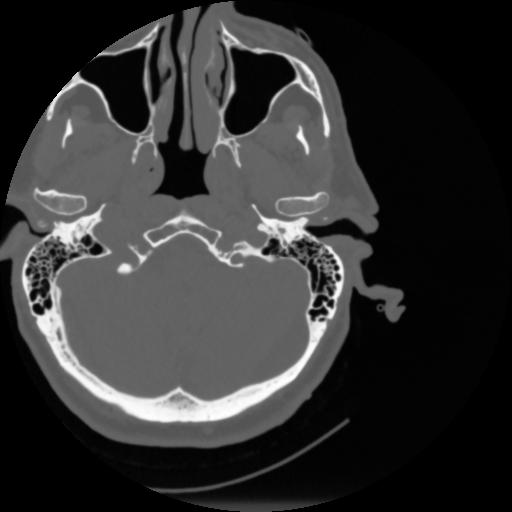

4 CEREBRO,,Vol,0.5,CEREBRO,,